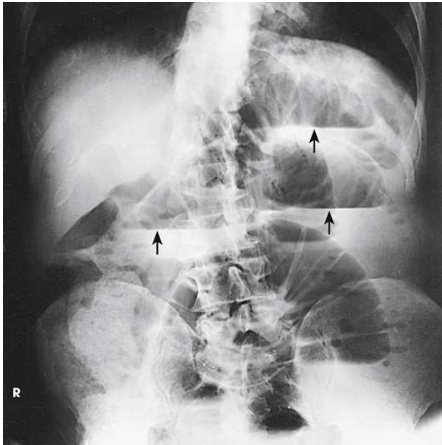

What projection, position, and anatomy is this?

left lateral decubitus